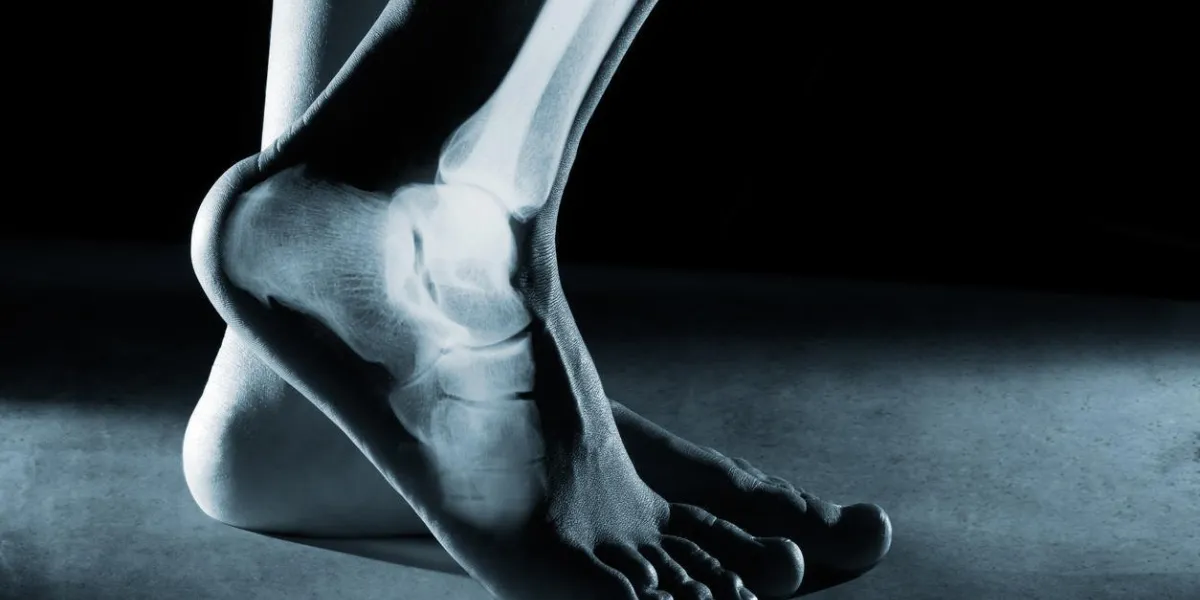

L'ostéoporose est une maladie osseuse caractérisée par une diminution de la densité osseuse et une détérioration de la structure osseuse, entraînant une fragilité osseuse accrue et un risque accru de fractures. Elle peut survenir chez les personnes de tous âges, mais est plus fréquente chez les femmes après la ménopause.

Les symptômes peuvent inclure des douleurs osseuses, des fractures spontanées ou une diminution de la taille. Les facteurs de risque incluent un faible apport en calcium, une carence en vitamine D, la sédentarité, le tabagisme et une consommation excessive d'alcool.